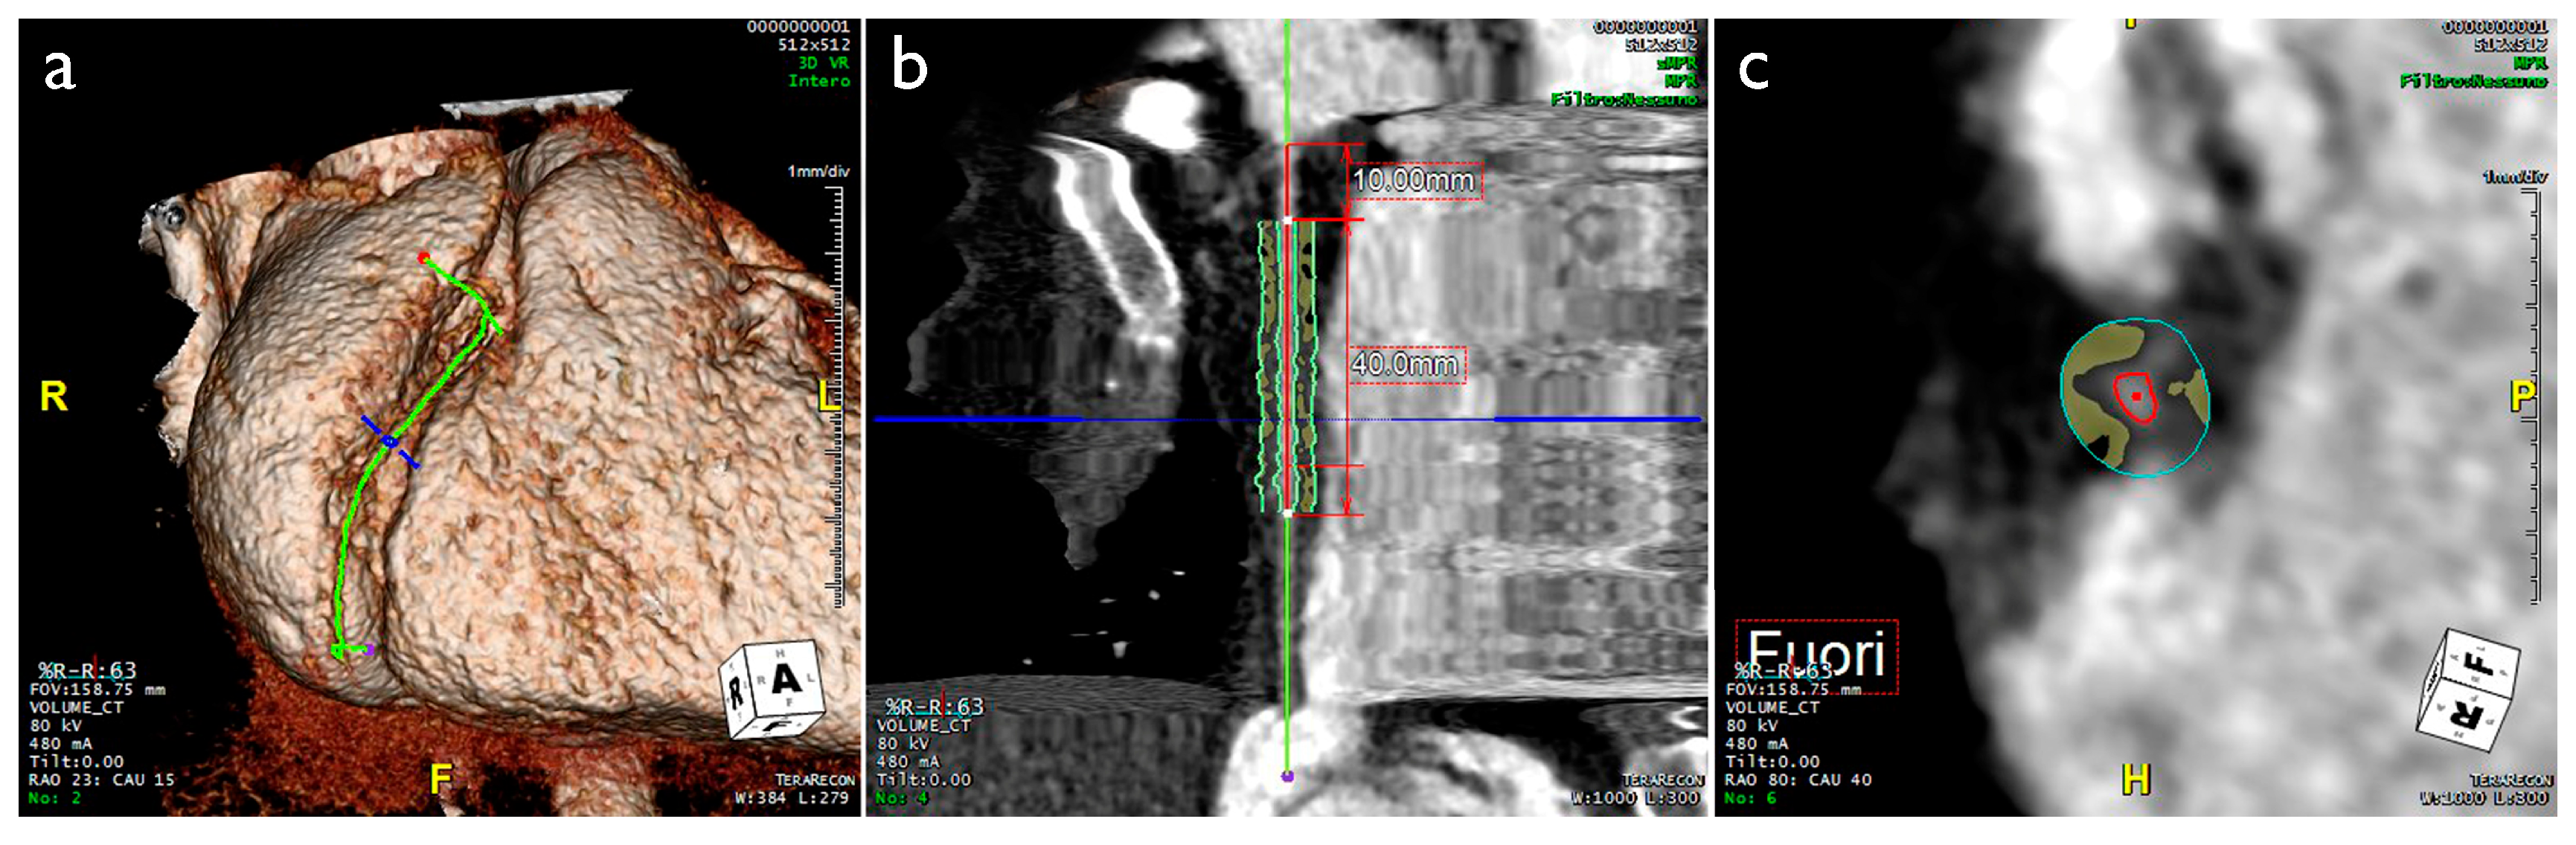

- Pergola, V.; Continisio, S.; Mantovani, F.; Motta, R.; Mattesi, G.; Marrazzo, G.; Dellino, C.M.; Montonati, C.; De Conti, G.; Galzerano, D.; et al. Spontaneous coronary artery dissection: The emerging role of coronary computed tomography. Eur. Heart J. Cardiovasc. Imaging 2023, 24, 839–850. [Google Scholar] [CrossRef]